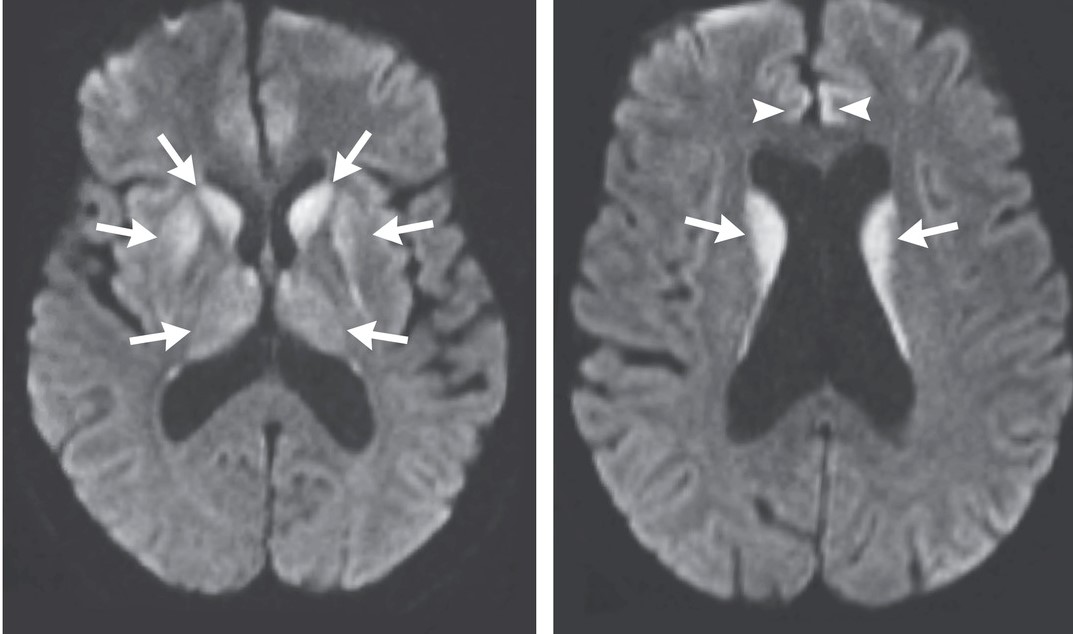

Her CBC and spinal fluid analyses are normal. The results of a MRI of the head

are shown below.

Axial diffusion-weighted images of the patient's brain. Arrows point to areas of hyperintensity in the basal ganglia and thalami and, less prominantly, the anterior cingulate gyri.